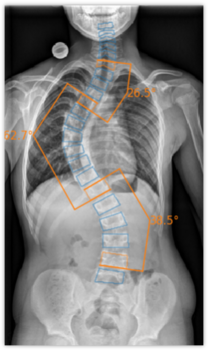

The underlying technology of ImageBiopsy Lab's software is based on machine learning. This means that computers learn from examples of previous cases. Thousands of X-ray images, manually marked by doctors, serve as training data: they point out to the software where joint spaces, bone angles, or fractures are located. The system learns to automatically recognize and measure similar structures in new images. ImageBiopsy Lab's solutions recognize relevant structures in seconds, measure defined parameters, and generate a structured analysis report – standardized and reproducible. This creates a reliable basis for diagnostics, follow-up care, and therapy decisions.

Today, ImageBiopsy Lab has seven certified modules (MDR/TÜV SÜD, partly also certified by the US FDA) on the market. They address key anatomical regions such as the knee, hip, spine, and foot, and provide standardized analysis reports that are used in radiology and orthopedic clinics in Germany, Austria, and Switzerland. Installed on-premise, they run in the background and deliver additional information directly to the image.